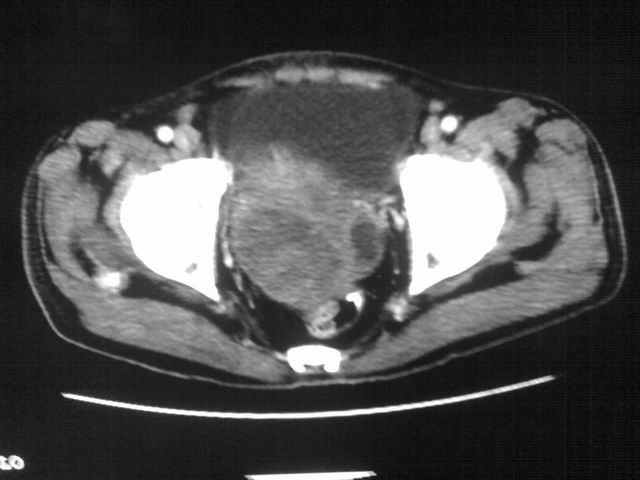

患者m 56岁,盆腔及下腹部胀痛半年,加重1月余,消瘦\中重度贫血.(附:平扫时直肠的高信号为,残留的钡剂).补一下病史:胃镜及纤维结肠镜均无明显异常.

膀胱后方及直肠前方见巨大混杂密度影,与前列腺相连且向膀胱内突入,精囊腺显示不清;考虑前列腺癌侵犯精囊、膀胱。

膀胱及直肠间有不规侧的软组织密度影,内密度不均匀。其内有坏死囊变,前列腺及精囊腺,膀胱后壁受浸。结合病史考虑腹膜后肉瘤可能性大。